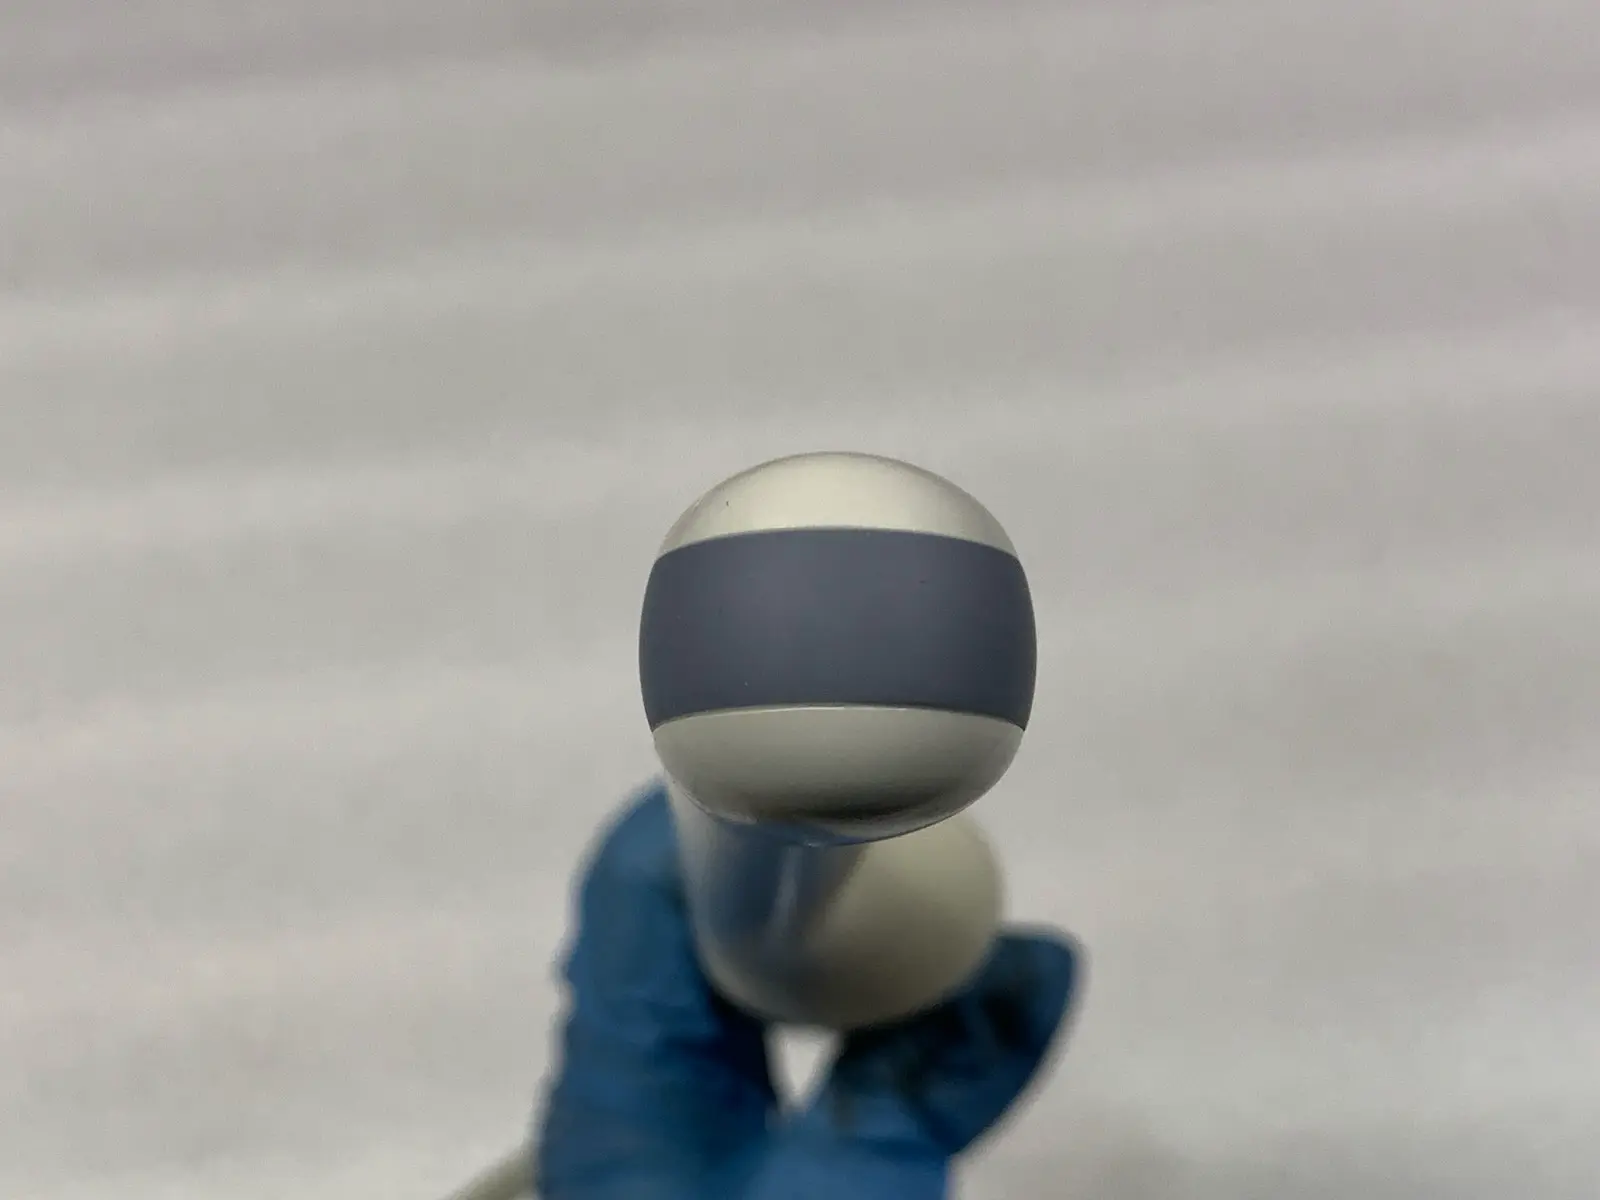

Acoustic Window (Lens): Appears clean and intact with no significant delamination or pitting visible in photos.

Blemish : Some cosmetic blemishes

Photos of this listing are of the actual item for sale.